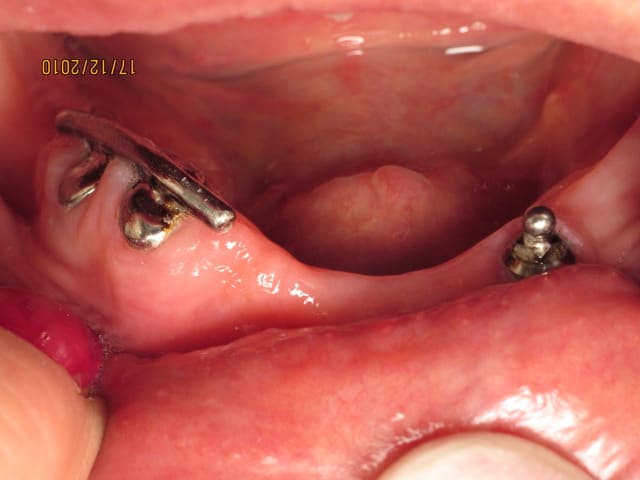

j'ai une patiente qui a un implant type boule qui se clippe sous son appareil complet.

je pense qu'il s'agit d'un Dalbo de chez cendre et métaux.

9a ressemble à un strauman de 4,1 avec une boule qui va avec; A confirmer à la radio.

Possible Dalbo décliné en plusieurs versions, mesure le diamètre de la boule, si 2,25 m/m bingo.

Pour ton cas, vu la configuration, le plus indiqué DalboPlus, tenir en compte auteur et volume de résine, voir renfort coulé pour prévenir fractures.

effectivement, c'est un dalbo de chez C&M.